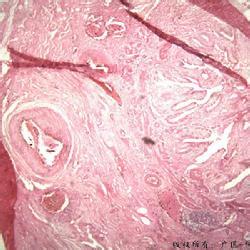

3.伴有结石的慢性萎缩性胆囊炎又称瓷瓶样胆囊,结石引起的炎症刺激,导致胆囊壁钙化而形成,钙化可局限于黏膜,肌层或两者皆有,多见于65岁以上的女性病人。

4.黄色肉芽肿样胆囊炎少见,系由胆汁脂质进入胆囊腔的结缔组织致炎性反应而成。